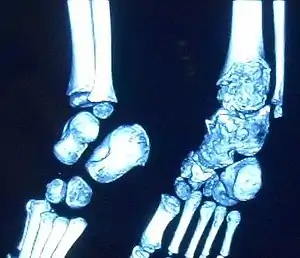

| Trevor disease in a 9 yr old girl: Talus | |

This disorder is rare, and is characterised by an asymmetrical limb deformity due to localized overgrowth of cartilage, histologically resembling osteochondroma. It is believed to affect the limb bud in early fetal life. The condition occurs mostly in the ankle or knee region and it is always confined to a single limb. This usually involves only the lower extremities and on medial side of the epiphysis. It is named after researcher David Trevor.[1]

Trevor disease was first described by the French surgeon Albert Mouchet and J. Belot in 1926. In 1956, the name "dysplasia epiphysealis hemimelica" was proposed by Fairbank.[1] The usual symptoms are the appearance of an osseous protuberance, on one side of the knee, ankle or foot joint which gradually increases Radiologically,[14] the condition shows a nonuniformity of growth and multiple unconnected ossification centers around the epiphyses.[8]